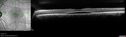

35 year old male Yesterday morning the patient woke up with poor vision in the left eye. Prior to that his vision was OK. PMHx benign. Blood pressure 154/115 mmHg. VA OD: Dcc20/16 NccJ1+ (-2) VA OS: Dcc20/40 PHNI NccJ16 IOP: TP: OD:22 OS:18 Lens clear – no uveitis Persistent fluid at 6 months required PDT laser - then fluid absorbed

Central Serous Chorioretinopathy - Expanding hot spot - photodynamic laser244 views35 year old man with acute central serous chorioretinopathy. The fluid got better then worse and the patient was treated with full strength juxtafoveal PDT and then got better.00000